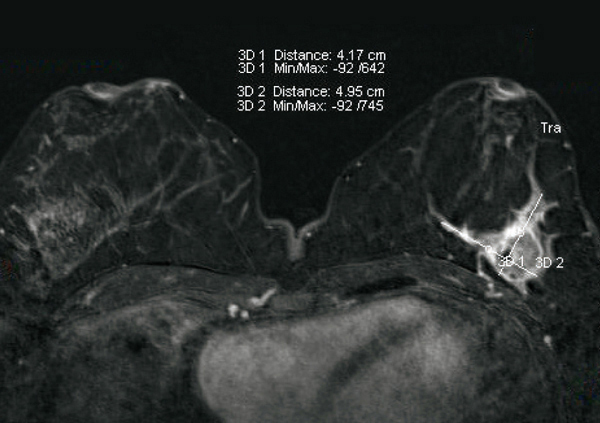

© Sylvie Lemery - La Revue du Praticien IRM, masse unique BIRADS 5. Histologie : carcinome canalaire type triple négatif.